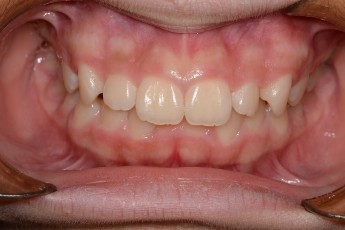

BEFORE & AFTER

- 덧니교정